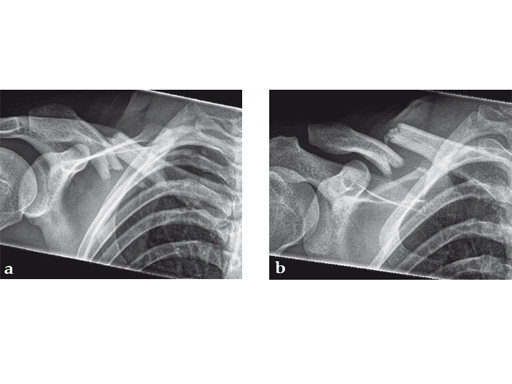

Case 2: a 29-year-old man sustained a midshaft clavicle fracture while playing soccer.

Case provided by Norbert Sdkamp and Martin Jaeger, Freiburg, Germany